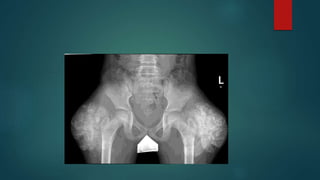

BONE TUMOR

Osteoid osteoma/osteoblastoma